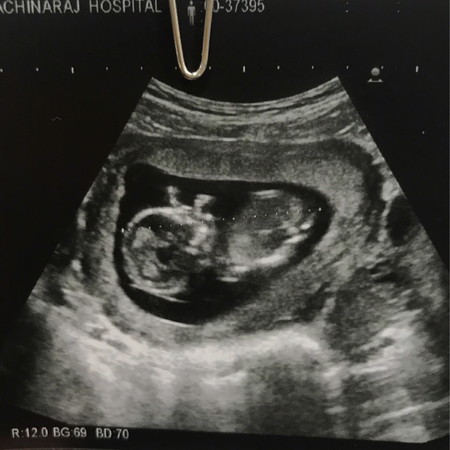

สงสัยว่าตรงหัวน้องคืออะไรค่ะ จะมีโผล่มา 2 ข้างบางคนบอกว่ามือค่ะ แต่เราไม่แน่ใจ ตอนเจอหมอก็ไม่ได้ถาม ใครทราบแจ้งทีนะคะ

มือข้างซ้ายคะ ข้างขวาชิดแก้ม